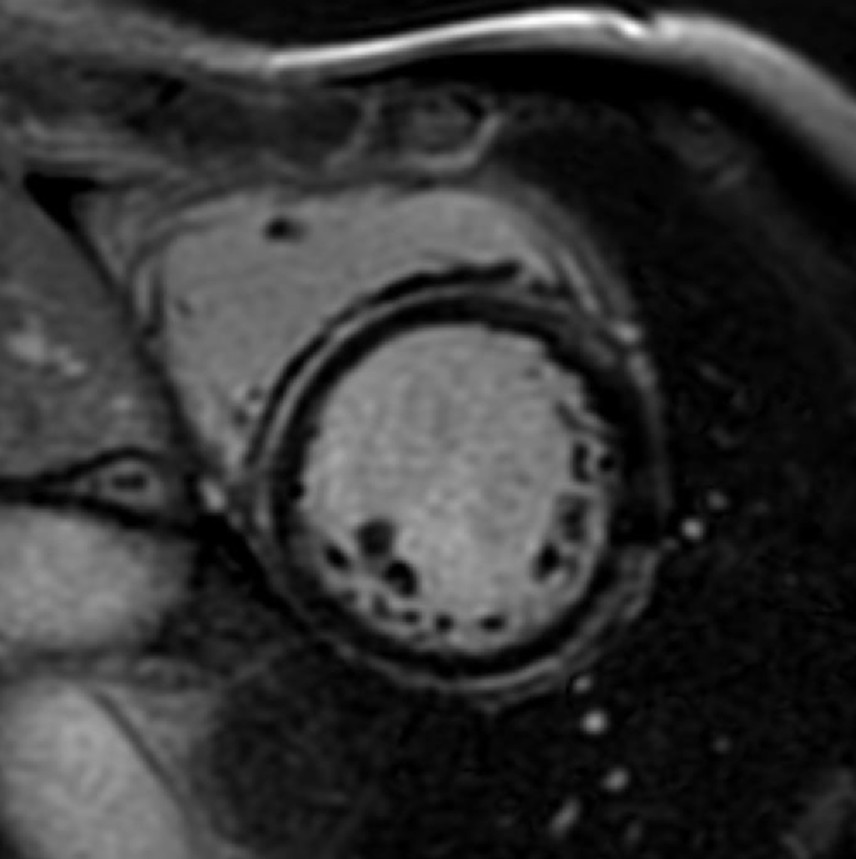

There is a world outside the stent mesh

Caso condiviso da Saima Mushtaq

Paziente con anamnesi di malattia coronarica e pregresso impianto di stent sulla discendente anteriore sinistra.

Per prima cosa, esamina l'intera scansione. Concentrati sul tronco comune e sulla porzione prossimale della discendente anteriore sinistra.